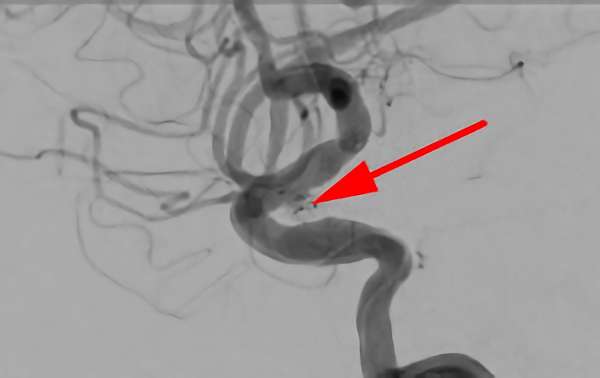

左椎骨動脈後下小脳動脈分岐部動脈瘤

70代

院内外来

No.1628 手術後